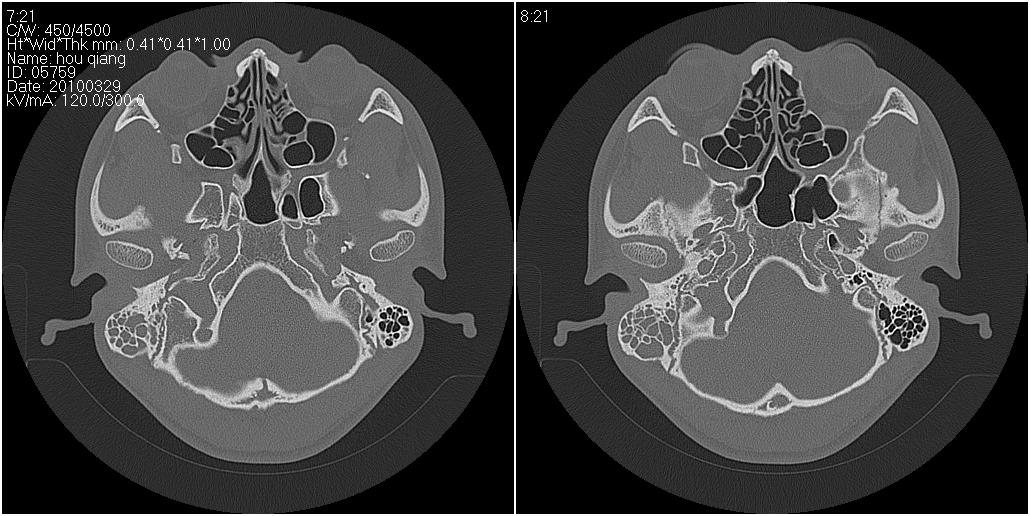

标题: CT25419:男性,18岁。右耳肿、痛5个多月。 [打印本页]

标题: CT25419:男性,18岁。右耳肿、痛5个多月。

右侧中耳乳突炎累及外耳道,鼻咽腺样体肥大。

1)右侧慢性中耳乳突炎并右侧中耳腔及外耳道肉芽肿或胆脂瘤形成。2)鼻咽腺样体肥大。